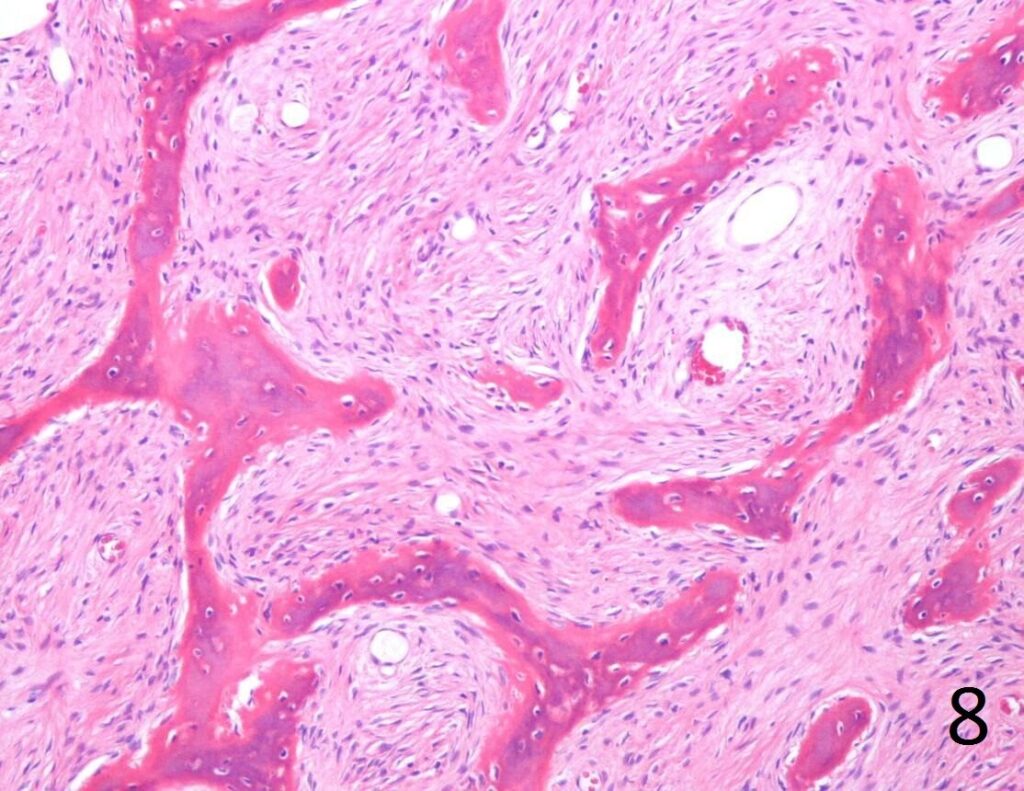

• Combination of bland hypocellular fibrous tissue with small fragments of woven bone without visible rimming by osteoblasts(Fig. 7-8) .

• The trabecule are common referred as Chinese characters, or resembling “Cs”and “Os”. Also may be called Alphabet Soup. This arrangement may mimic the appearance of Paget’s diseases

• Trabeculae are not lined with oteoblasts.

Fig. 8. Microscopic: Low power photograph of fibrous dysplasia shows a combination of bland fibrous tissue with small fragments of woven bone.